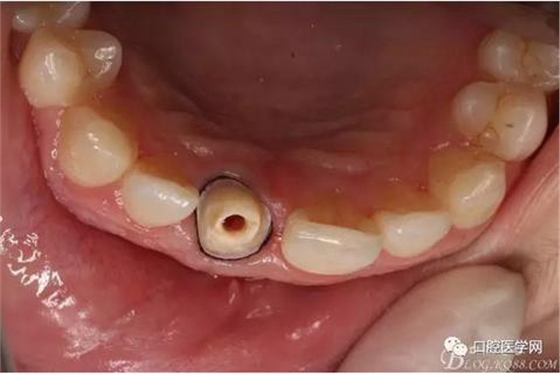

檢查:11殘根,烤瓷冠脫落,部分充填材料和折斷的纖維樁存于內(nèi)冠。唇側(cè)牙齦紅腫,基牙肩臺在齦下2毫米,根尖區(qū)觸診無不適,黏膜無紅腫,無瘺管口。叩診(-)??谇逍l(wèi)生一般。

纖維樁+樹脂核

樁道長14mm

備牙